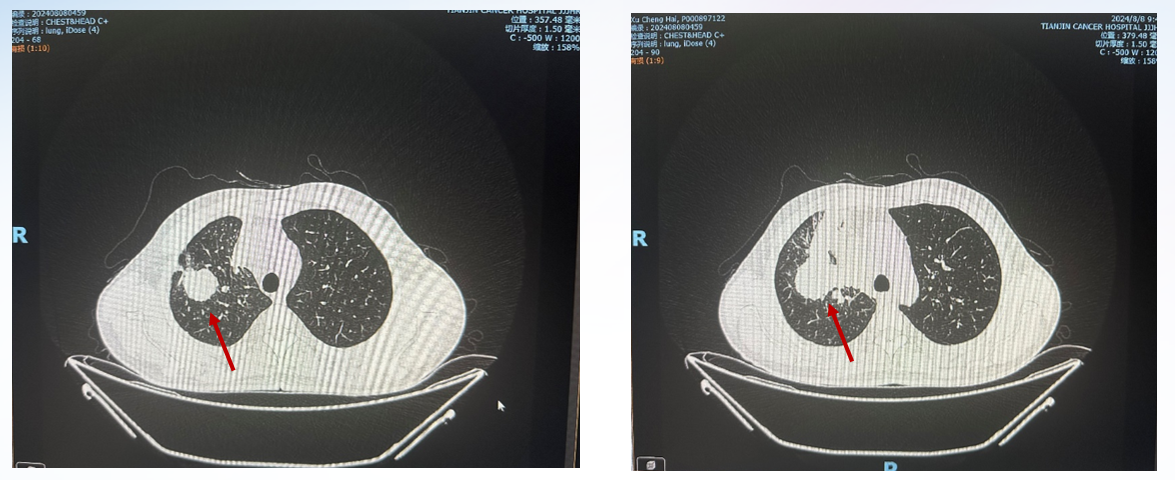

2024-08-08 头胸增强CT(图1)示:1.与2024-07-10外院胸部片比较,右肺上叶及右肺门软组织肿物伴周围实变不张,整体范围较前有所增大;余无显著变化;2.与2024-07-09外院头颅CT片比较,未见明显变化,必要时MR检查。

图1 头胸增强CT(2024-08-08)

2024-08-08,查胸部CT较2024-07-10病灶范围增大。

疗效评估:PD。

PFS1:1个月。